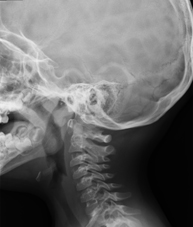

- RX Charnela

Técnica mediante la cual, utilizando rayos X, se obtienen imágenes de la charnela o de la base del cráneo para su estudio. Indicaciones: estudio de malformaciones congénitas.